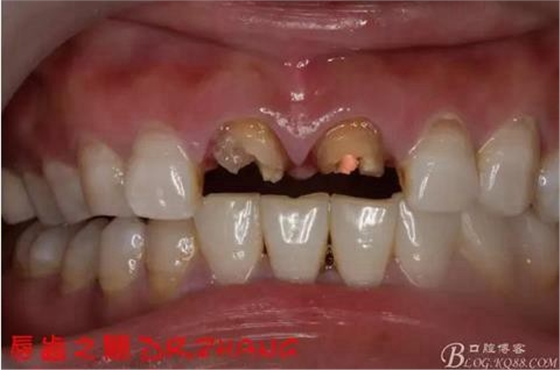

主訴:左上門牙腫脹數(shù)日

現(xiàn)病史:患者自訴兩年前在外院做了門牙的修復(fù) 一個(gè)月前左上門牙腫 服藥后消腫 前幾日腫脹厲害 影響正常生活 現(xiàn)來(lái)我院 要求治療

檢查:11 21金屬烤瓷冠 21根尖部牙齦紅腫 牙痛 叩(+++)冷刺激無(wú)反應(yīng) 11無(wú)不適癥狀 全口牙周情況良好